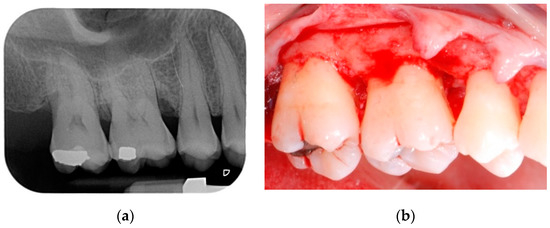

Patients were prescribed with doxyciclin 100 mg (2 tablets on the first day and then one tablet per day for 14 days) and ibuprofen 600 mg (2 tablets per day for 5 days). Three patients, who had previously reported recurrent gastritis, were also prescribed with pantoprazole 20 mg (one tablet every morning before breakfast for 10 days). Patients were instructed not to brush the treated area, but to rinse their mouth twice a day using a 0.20% chlorhexidine mouthwash, starting from the day after the surgery until suture removal. A cold diet and ice packs application were recommended for the first day after surgery. All patients were seen 7 days post-op; a second check was scheduled 2 weeks after the surgical procedure; at this time, the sutures were also removed. For the first 12 months after surgery, patients were scheduled for supportive periodontal therapy recalls every three months (Figure 3a,b).

Figure 3.

(a) Clinical view of the treated area at 12-month follow-up; (b) periapical radiograph at 12-month follow-up.